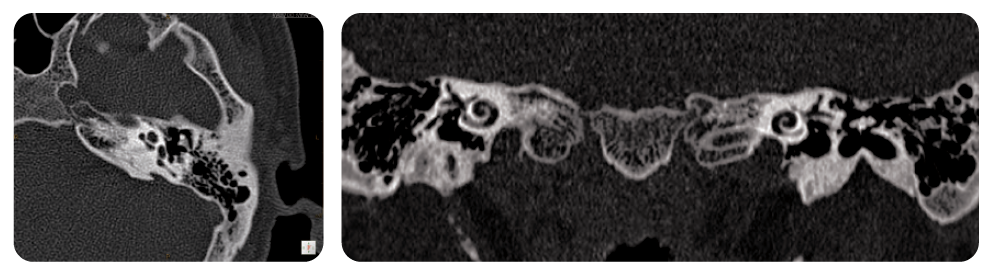

Matricea de Reconstrucție 1024

Tehnologia de reconstrucție cu matrice 1024 oferă rezoluția spațială necesară pentru studiile de noduli pulmonari și ureche internă.

Imagini de Înaltă Rezoluție a Urechii Interne

Reformarea multiplanară coronară și axială arată structurile mici ale urechii interne, cum ar fi cohlee și canalele semicirculare